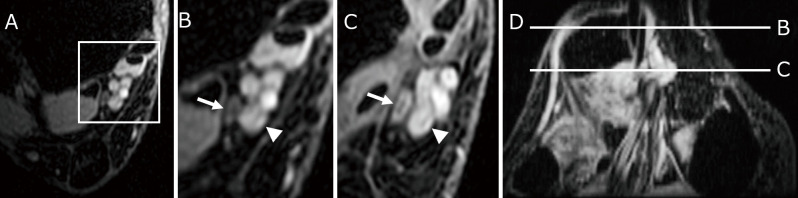

跗骨隧道综合征是一种位于跗骨隧道的压迫性神经病变。诊断和预测手术结果是困难的。我们比较了术前和术后的磁共振成像结果。我们检查了连续38例跗骨隧道综合征(47英尺)患者的术前磁共振成像结果;他们的平均年龄为73.8岁。我们在术前T2*脂肪抑制轴向磁共振成像图像上观察最受压神经切片上的神经宽度和该神经的高强度,并探讨磁共振成像在跗骨隧道综合征患者的诊断和手术结果中的作用。术后症状明显改善。术前磁共振成像扫描显示,最受压神经的平均宽度为0.99±0.37 mm。术前症状严重程度与术后症状改善无显著相关性。在29英尺(61.7%),我们观察到压迫神经的高强度。除一只脚外,其余足部均在靠近最强神经压迫点的3个轴向切片上显示高信号区。术前有高强度(1组,n = 29)和无高强度(2组,n = 18)患者的症状严重程度无显著差异。组1患者最大受压点神经宽度明显变细,术后症状改善明显较大。虽然术前神经压迫严重程度与手术结果之间没有相关性,但磁共振成像扫描显示的神经高强度可能有助于跗骨隧道综合征的诊断。

Tarsal tunnel syndrome is an entrapment neuropathy at the tarsal tunnel. The diagnosis and the prediction of the surgical outcome are difficult. We compared preoperative magnetic resonance imaging findings with the postoperative results. We examined preoperative magnetic resonance imaging findings in 38 consecutive patients with Tarsal tunnel syndrome (47 feet); their mean age was 73.8 years. We inspected the nerve width on the slice showing the most compressed nerve, and the hyperintensity of that nerve on preoperative T2* fat-suppressed axial magnetic resonance imaging images and examined the role of magnetic resonance imaging in the diagnosis and of the surgical outcomes in patients with Tarsal tunnel syndrome. Postoperatively, there was significant symptom improvement. On preoperative magnetic resonance imaging scans the mean width of the most compressed nerve was 0.99 ± 0.37 mm. There was no significant correlation between the preoperative symptom severity and postoperative symptom improvement. In 29 feet (61.7%) we observed hyperintensity of the compressed nerve. In all but one foot the hyperintense area was displayed on 3 axial slices adjacent to the strongest nerve compression point. There was no significant difference in the preoperative symptom severity in patients with (group 1, n = 29) or without hyperintensity (group 2, n = 18). The nerve width at the point of greatest compression was significantly thinner, and postoperative symptom improvement was significantly greater in group 1 patients. Although there was no correlation between the preoperative nerve compression severity and the surgical results, nerve hyperintensity on magnetic resonance imaging scans may help with the diagnosis of Tarsal tunnel syndrome.